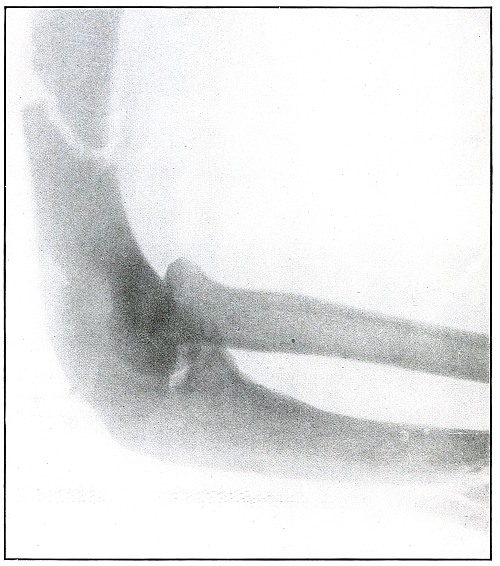

[Pg 46]

Plate 18.

[Pg 47]

Rifle—Plate 18.

UPPER EXTREMITY.

Gunshot Fracture of the Elbow,

without Injury to the Great Vessels and Nerves.

Wound of entrance, posterior to the external condyle.

Wound of exit, large laceration in front and above the internal condyle.

The wound is an example of the misnamed “explosive” action of a rifle

bullet. The force and direction of the missile, in high velocity,

split the bone into many fragments, and, transmitting its energy to

some of the fragments, carried them through the skin and caused the

large laceration at the point of exit by the simultaneous escape of

the bullet and fragments. The wound was so heavily infected, that a

cellulitis advanced to the shoulder and to the wrist to such extent

that the arm was marked by eminent surgical opinion for amputation.

Free incision, drainage, antisepsis and incidental removal of detached

fragments controlled the infection and brought about slow resolution.

After six months of careful treatment the wound was healed with an

ankylosed elbow with normal function of the forearm, except for

limited rotation.

Treatment indicated in such cases is always conservative. Infections

contraindicate any formal surgical interference. The dangers of

infection in such cases are to be risked to avoid amputation.

Results may be considered favorable even with elbow ankylosis.